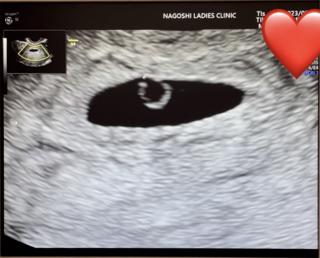

胎嚢は約1cmで順調に育っていて、卵黄嚢もクッキリ見えました!

1週間後に心拍の確認。

お薬は9週目まで続けるとのこと!

前回は化学流産だったから1歩進んでホッと。